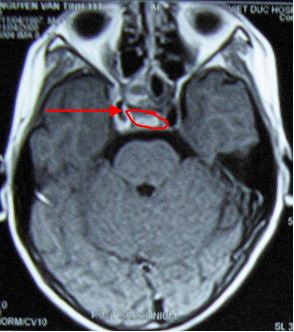

2. Bệnh nhi Nguyễn Viết T., nam 11 tuổi.  Vào viện vì đau đầu, mờ mắt phải, sụp mi mắt phải. Cách ngày vào viện 4 tháng bệnh nhân đau đầu và mờ mắt ngày càng tăng dần, sau đó sụp mi mắt phải. Tại bệnh viện Bạch Mai bệnh nhi (BN) được chẩn đoán khối u màng não vùng nền sọ và hốc mắt phải đường kính 31x55x23mm, xâm lấn xoang bướm và bao quanh động mạch cảnh trong phải. BN được chỉ định điều trị xạ phẫu gamma knife liều 14Gy. Sau điều trị khoảng 1 tháng thị lực mắt phải của bệnh nhi được cải thiện nhiều (trước điều trị thị lực mắt phải 1/10; sau điều trị 7/10) hết đau đầu và sụp mi. Trên phim chụp cắt lớp vi tính sọ não: hình ảnh khối u đã thu nhỏ kích thước hơn trước

Hình  ảnh u  trước  điều  trị:  khối  u  màng não vùng nền sọ và hốc mắt  phải  đường kính 31x55x23mm, xâm lấn xoang  bướm và bao quanh động mạch cảnh trong phải

Sau điều trị 1 tháng: khối u thu nhỏ kích  thước hơn trước, đường kính 20x15mm